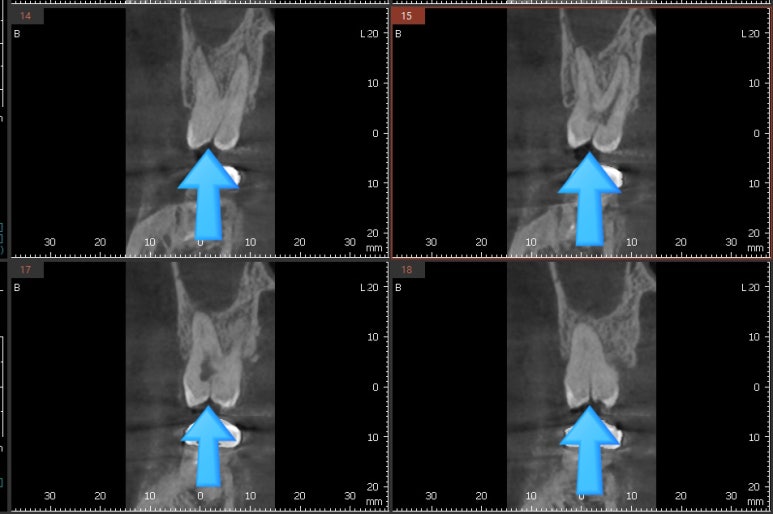

세로로 금이 간 것이 3차원 ct에서 희미하게 보입니다.

아주 미세한 금은 ct에서 안보일수도 있습니다.

3차원 ct에서 간혹 치아가 금이 간 것을 볼 수도 있습니다.